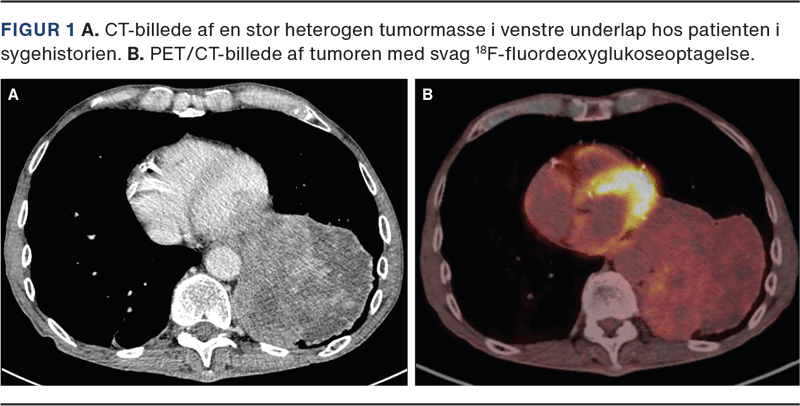

CT viste en heterogen tumorproces, der inddrog næsten hele venstre underlap uden tegn til invasion af de omgivende strukturer (Figur 1A). PET med lavdosis-CT viste kun svag fluordeoxyglukose (FDG)-optagelse forenelig med lavmalign proces (Figur 1B). De efterfølgende nålebiopsier fra tumoren blev vurderet bedst forenelige med SFT.

På grund af tumorernes variable udseende og forskellige lokalisationer i thorax kan CT-fund ved SFTP være diagnostisk udfordrende. Større SFTP er typisk heterogene, som hos patienten i sygehistorien, og i disse tilfælde kan både benigne og maligne SFTP minde om andre maligne processer [4]. PET-CT kan muligvis bidrage til at differentiere mellem SFTP og andre maligne lidelser, og mindre studier har vist svagere FDG-optagelse ved maligne SFTP sammenlignet med andre maligne tumorer i thorax [4]. En endelig diagnose kræver dog histologisk bekræftelse [1].